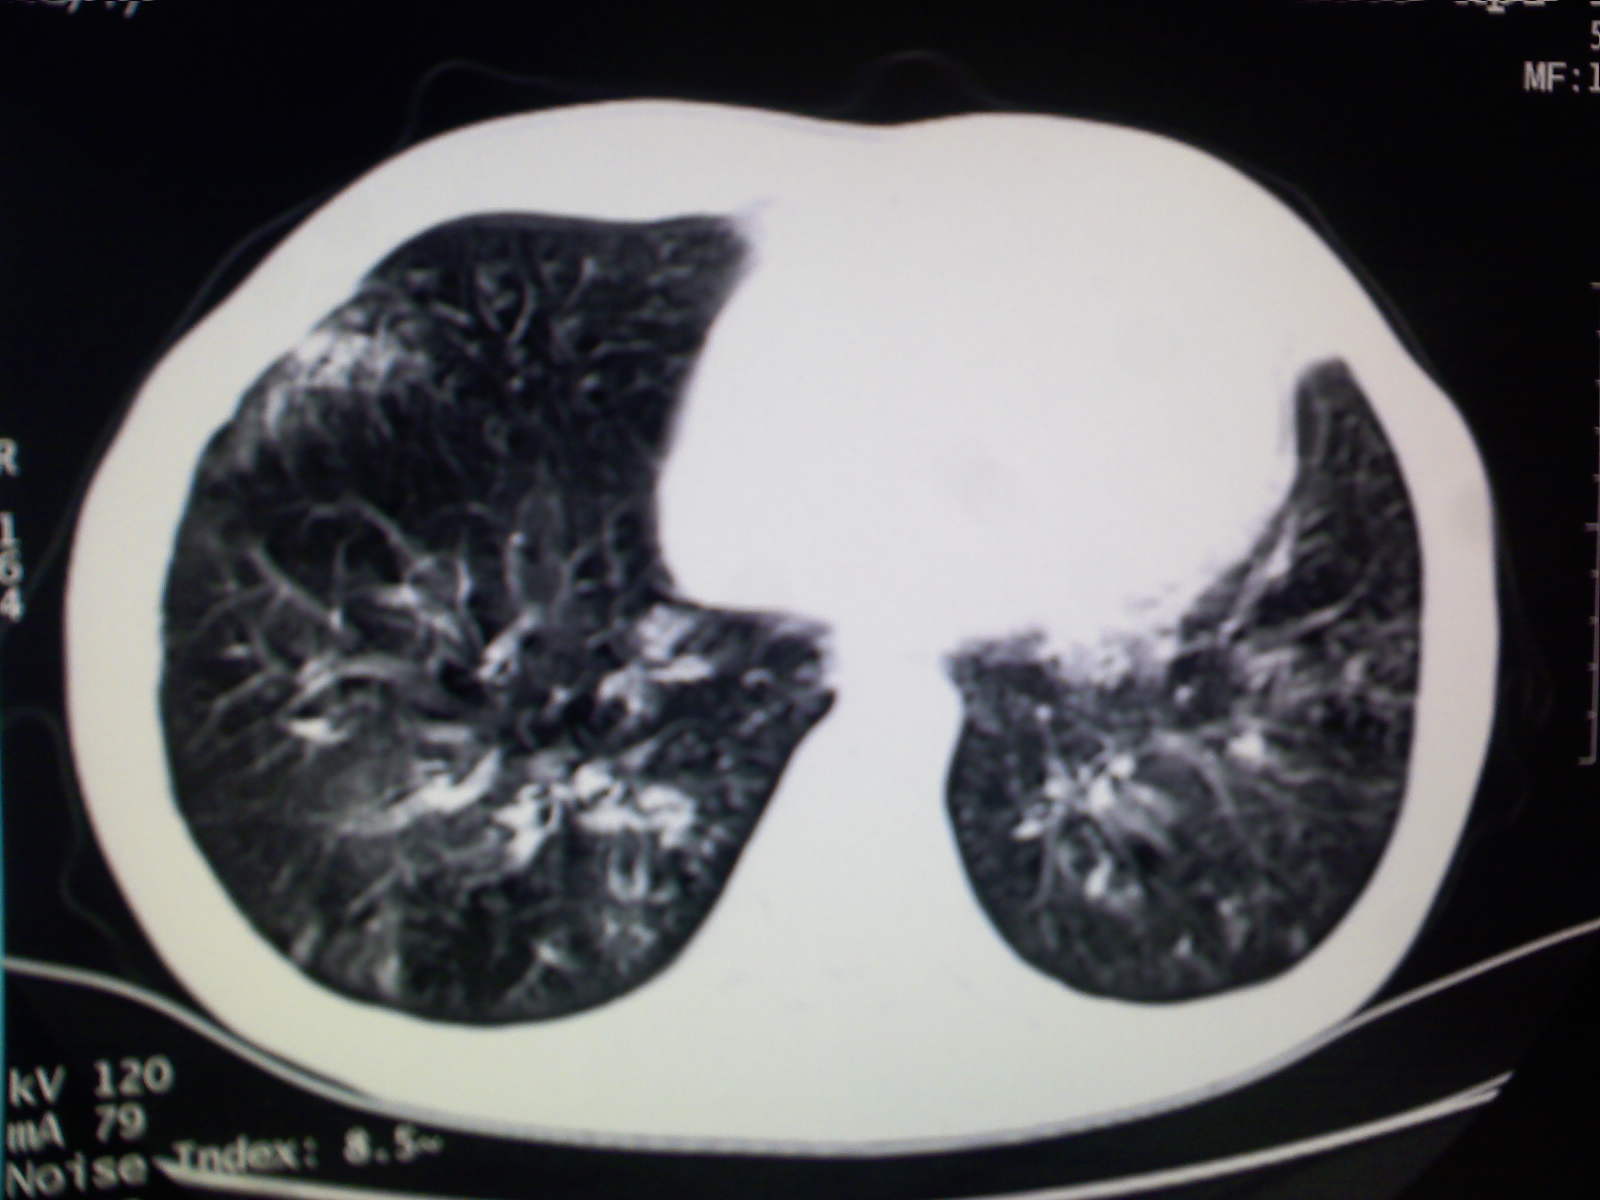

以下是引用卜一在2009-4-11 15:50:00的发言:[br]双肺继发性肺结核伴空洞形成,不排除合并霉菌感染!(病灶呈多形态 多特征 散在分布)。另:合并支气管扩张征伴感染!

以下是引用主力军在2009-4-11 15:55:00的发言:[br]两肺继发性肺结核可能性大。

以下是引用康鹏在2009-4-11 16:30:00的发言:[br]双肺继发性肺结核伴空洞形成合并感染[br]支气管扩张合并感染